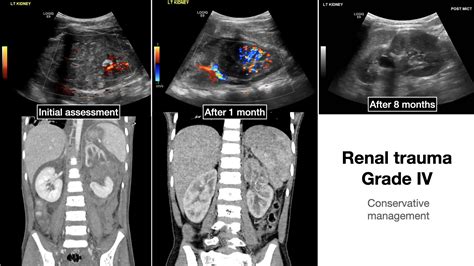

Renal Trauma

Ultrasound

Grade 4